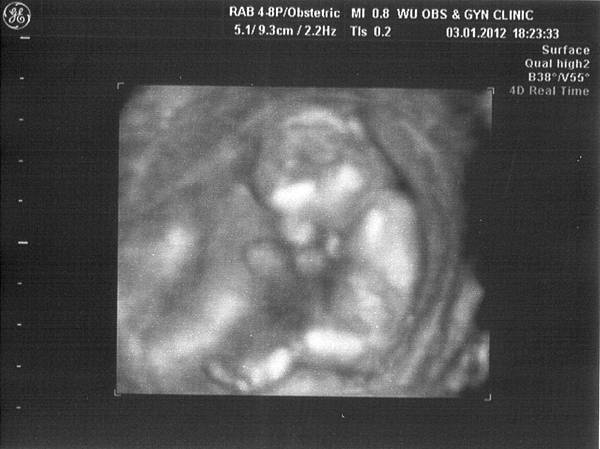

雖然這次不是產檢,但還是有機會看到小寶貝的模樣

除了還是雙腳閉閉不讓我們看個啾竟之外,

還一手遮住臉很害羞的模樣,

寶寶~你真的好害羞喔,跟媽咪一樣啦(羞)

林醫生確認胎盤、羊水的狀況都很正常,

也就是基本上搭飛機不會有什麼太大問題,